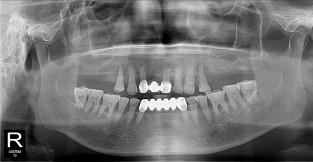

• 9

무치악

치료기간 : 2023-02-21 ~ 2023-10-21

1. 상기 x-ray 이미지 모두 동일한 해당 의료기관에서 진료한 환자입니다.

2. 상기 x-ray 이미지 모두 동일 인물의 것입니다.

3. 치료 전 이미지는 2023-02-21에 촬영했으며, 치료 후 이미지는 2023-10-21에 촬영하였습니다.

4. 상기 x-ray 이미지 모두 동일 조건에서 환자분의 동의를 받아촬영되었습니다.

* 임플란트 시술은 환자분의 상태(고혈압, 당뇨 등)에 따라 부작용이 있을 수 있으니, 반드시 전문의와 상담이 필요합니다.

* 임플란트 수술 부작용

: 수술 후 출혈, 교합, 통증, 붓기, 염증 등의 문제점이 발생할 수 있습니다.)